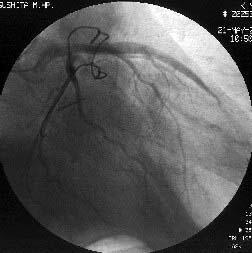

徢椺丗61嵨丄抝惈丅

婛墲楌丗58嵨帪偵DeBakey II宆偺媫惈戝摦柆夝棧偵偰Bentall弍(Piehler朄)傪巤

峴丅59嵨帪偵偼暊晹偵媫惈戝摦柆夝棧傪敪徢偟丄堦帪峈嬅屌椕朄傪拞抐偟偨偑偦

偺屻嵞奐丅

尰昦楌丗暯惉14擭5寧屵慜0帪傛傝摢栩晹捝偑弌尰偟丄嫻晹傊捝傒偑曻嶶偡傞傛偆

偵側傝7帪偵摉堾傪媬媫庴恌偝傟傑偟偨丅

棃堾帪尰徢丗寣埑86/66mmHg丆柆攺106/min丒惍丅岥怬偵僠傾僲乕僛傪擣傔偨丅怱

揹恾偱QRS暆偺奼戝偲I, aVL, V4-6偵ST忋徃傪擣傔丄媫惈怱嬝峓嵡偵傛傞怱尨惈

僔儑僢僋偲恌抐偟丄嬞媫僇僥乕僥儖専嵏傪巤峴偟傑偟偨丅

怱憻僇僥乕僥儖専嵏丗RCA偵嫹嶓昦曄傪擣傔傑偣傫偱偟偨偑丄LCx傊collateral傪

擣傔傑偟偨乮Figure1乯丅堷偒懕偄偰LCA偺憿塭傪帋傒傑偟偨偑丄JL僇僥乕僥儖偑

偳偆偟偰傕engage偱偒傑偣傫偱偟偨丅戝摦柆憿塭傪巤峴偟丄塃姤愲偺塃懁忋曽偵

憿塭嵻偺pooling傪擣傔傑偟偨乮Figure2乯丅擖岥晹偱姰慡暵嵡偟偰偄傞偲峫偊摨

晹埵偵懳偡傞僀儞僞乕儀儞僔儑儞傪巤峴偡傞偙偲偲偟傑偟偨丅擖岥晹偑塃懁忋曽

偵懚嵼偡傞偨傔丄僈僀僨傿儞僌僇僥乕僥儖偼丄JR僇僥乕僥儖傪巊梡偟傑偟偨

乮Figure3乯丅

側偍丄恖岺寣娗偺擖岥晹偺摨掕偵旕忢偵擄廰偟丄専嵏奐巒屻偡偱偵栺30暘偑宱夁

偟偰偄傑偟偨丅屇媧忬懺偑偝傜偵埆壔偟偮偯偗偨偨傔丄恖岺屇媧娗棟偲偟傑偟

偨丅寣埑傕掅壓偟偰偄傑偟偨偑丄DOA5兞掱搙偱80-90戜傪堐帩偟偰偄傞忬嫷偱偟

偨丅IABP偺憰拝傕峫偊傑偟偨偑丄戝摦柆夝棧偑懚嵼偟偰偄傞偨傔巊梡偟傑偣傫偱

偟偨丅

姤摦柆僀儞僞乕儀儞僔儑儞丗僈僀僨傿儞僌僇僥乕僥儖偺engage偑埆偄偨傔丄儔僕

僆僼僅乕僇僗丒儚僀儎乕偱僇僥乕僥儖傪屌掕偝偣側偑傜彊乆偵儚僀儎乕傪恑傔偰

偄偔偲丄彮偟偯偮寣娗偑憿塭偝傟傞傛偆偵側傝丄恖岺寣娗偲LMT偺暙崌晹偵崅搙

嫹嶓傪擣傔傑偟偨乮Figure4乯丅傑偨丄嵍姤摦柆撪偵嫄戝側寣愷傪擣傔傑偟偨丅

摉帪寣愷媧堷偺僨僶僀僗偑側偔丄媧堷偼偱偒傑偣傫偱偟偨丅暙崌晹偵懳偟偰丄

MAVERICK4.0mm偱POBA傪峴偄丄偦偺屻LAD偵嫄戝側寣愷偑棳傟偰偄偔偺偑妋擣偝傟

傑偟偨乮Figure5乯丅NIR4mm僗僥儞僩傪棷抲偟暙崌晹嫹嶓偼夵慞偟傑偟偨偑丄LAD

偺no flow傪擣傔傑偟偨丅nicorandil偍傛傃UK傪姤拲偟偨偲偙傠丄flow偑夵慞偟

偨偨傔庤媄傪廔椆偟傑偟偨乮Figure6乯丅